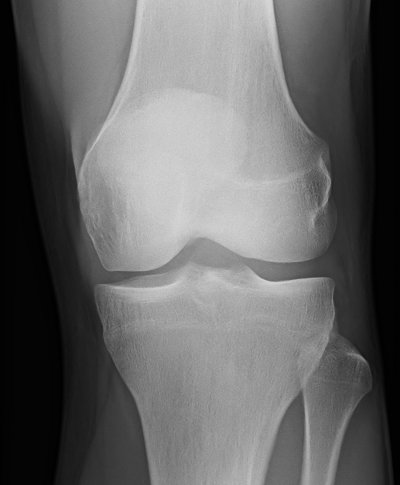

- Degenerative Gelenkerkrankungen (Arthrose)

Abnutzungserscheinungen an den Gelenken / Gelenkverschleiß

Behandlungsbeispiel

Die Orthovolttherapie ist eine schmerzfreie, nichtinvasive Behandlung mit speziellen energetischen Röntgenstrahlen.